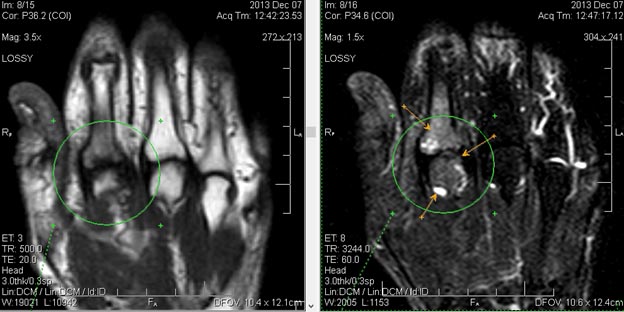

Для установления точного диагноза необходимо провести всестороннее обследование пациента. Это включает детальный осмотр ревматолога и других узкопрофильных специалистов. Обязательно назначаются общий и биохимический анализы крови, а также иммунологическое исследование. Важно выполнить следующие инструментальные исследования:

- миелограмма;

- рентгенография;

- УЗИ селезенки и суставов;

- КТ.

Часто рекомендуется МРТ, которое предоставляет детальную информацию о состоянии пациента. В некоторых случаях может быть назначена биопсия тканей.